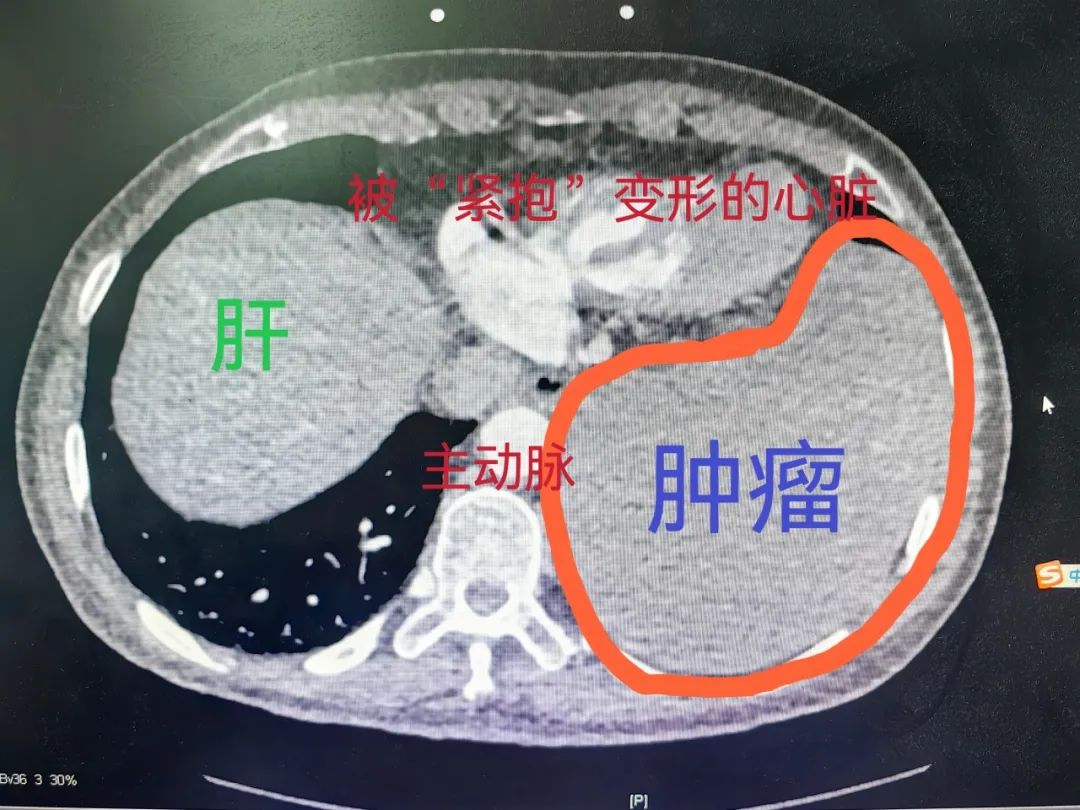

▲术前影像检查报告

经过进一步检查,结果显示她的左侧后胸腔巨大均质占位,如“枕头”一样,将心脏紧紧怀抱其中;在侧方,肿瘤下半部与降主动脉壁分界不清,有侵犯主动脉外膜可能;在后方,肿瘤与脊柱椎间孔关系密切,有向椎孔内“伸手”的嫌疑;向下方,肿瘤“霸气”地坐在膈面上,左侧肝脏受压。不仅如此,患者左侧下肺组织长期不张,已出现中度混合性通气功能障碍,术前肿物穿刺病理也提示为孤立性纤维肿瘤。